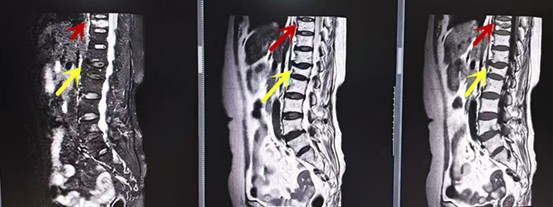

利器二:CT

CT利用X射线对人体检查部位通过电脑切成若干层扫描,然后把每层的图像都能显示出来。CT相对于X光片具有更高的密度分辨力,可直接显示X线片无法显示的病变,观察腰椎有无微小的骨折、骨质有无破坏等骨质情况、以及腰椎间盘突出、腰椎神经根、椎管、椎间小关节的情况等。同时还可以通过后处理,重建腰椎矢状位或冠状位图像,形成腰椎的3D图像,更直观地观察病变部位,对腰椎手术风险具有提示作用,对手术方式的选择具有指导意义,但是对神经、脊髓损伤程度的显示不如MRI,软组织的分辨率仍有一定限制,对椎管内病变显示欠佳,且有一定的辐射。

从左向右依次为CT矢状位重建图像、三维重建图像、轴位扫描图像,箭头提示腰1椎体爆裂性骨折